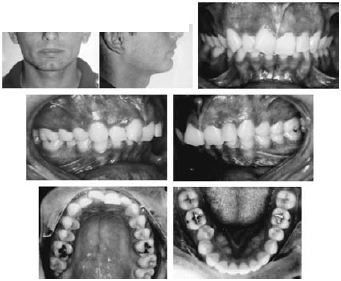

Um paciente apresenta má oclusão em que há envolvimento esquelético, por ter uma idade fora do período de crescimento. Os procedimentos ortopédicos, nesse paciente, são contra-indicados. Além disso, o paciente refutou a idéia de tratamento ortocirúrgico, restando apenas a possibilidade de compensação dentária, com risco de prejuízo estético. As ilustrações e os dados a seguir são referentes a esse paciente.

- discrepância de modelo do arco inferior: -4,00 mm

- discrepância de modelo do arco superior: -9,00 mm